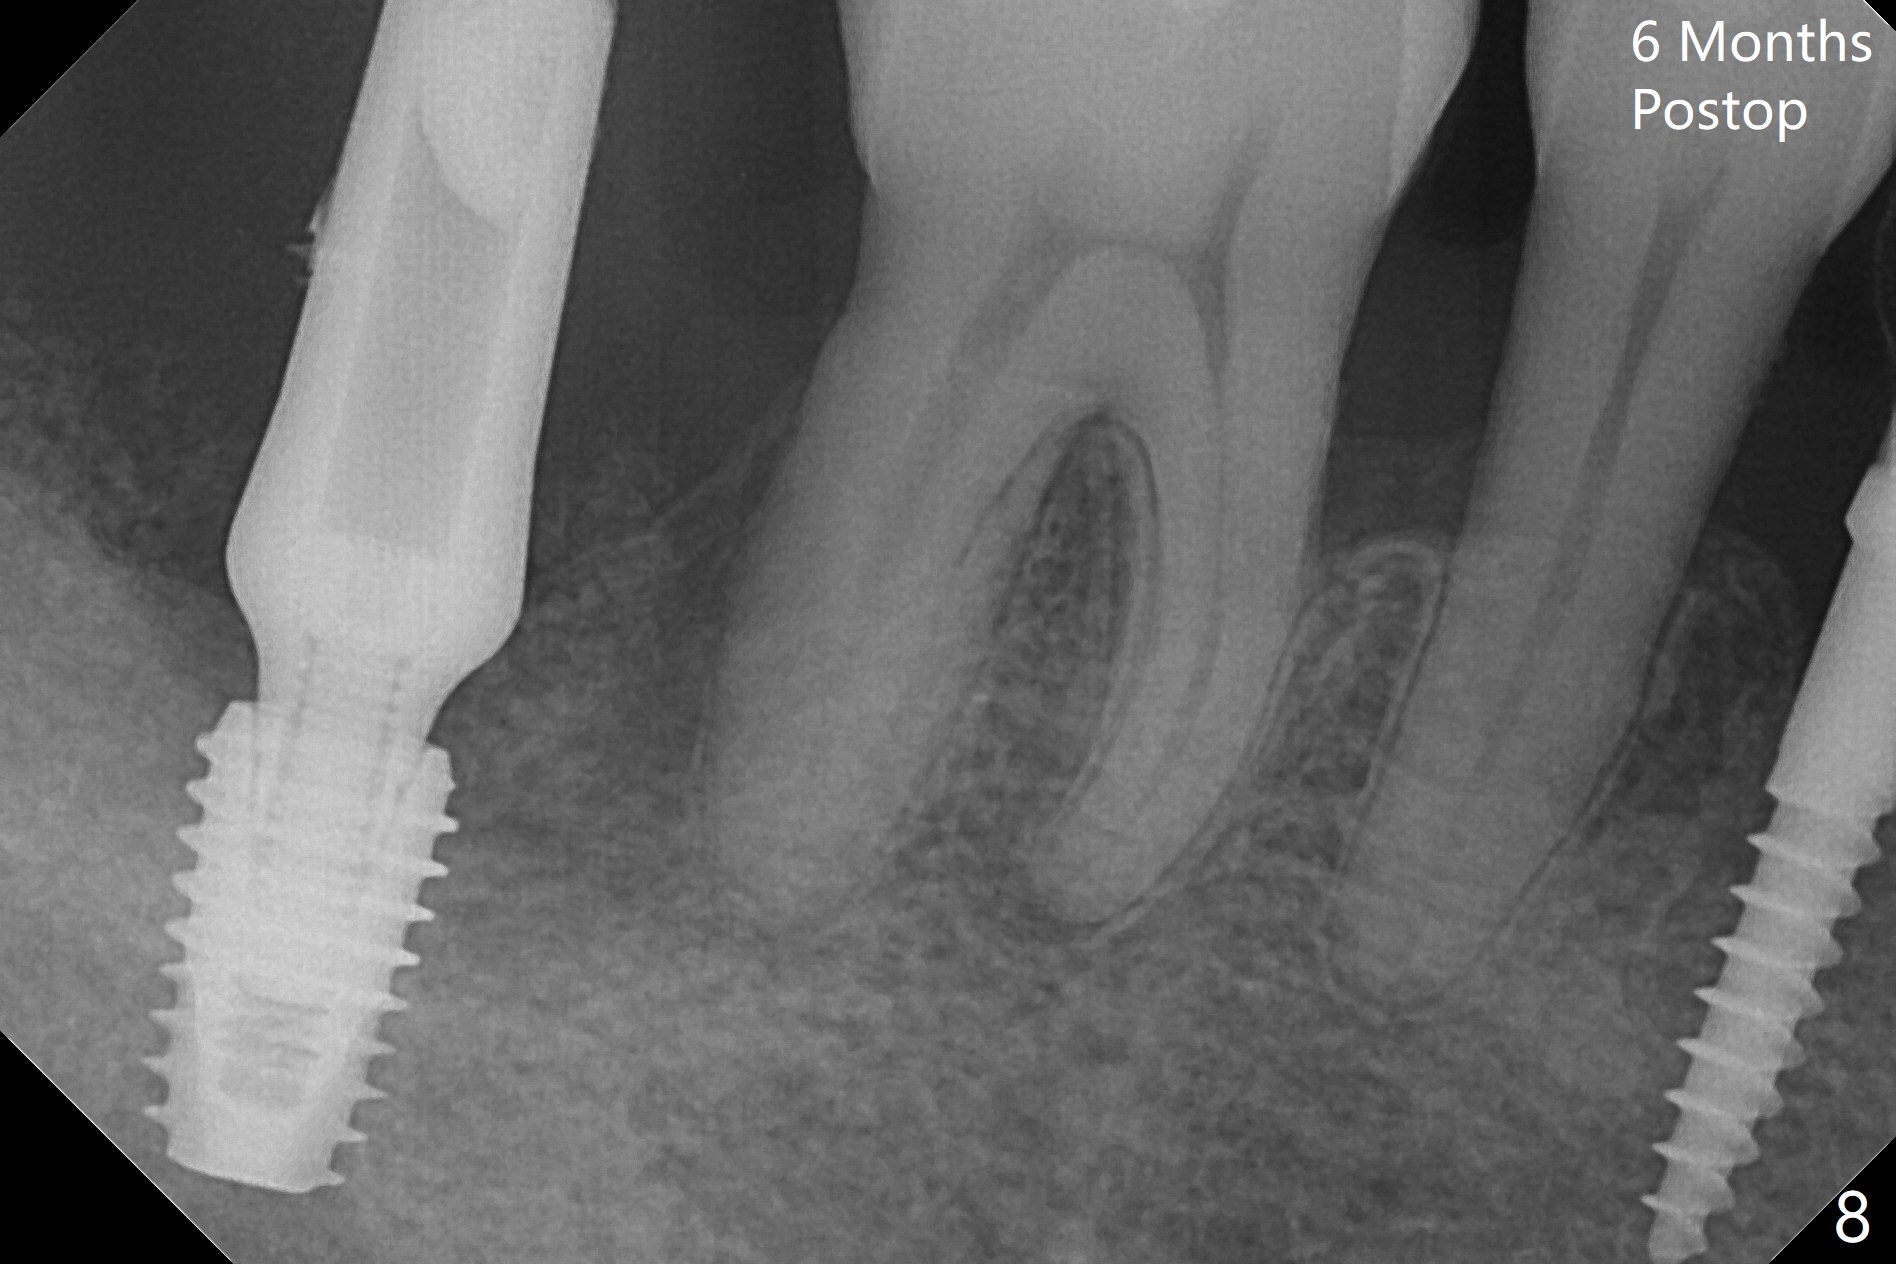

The affected tooth (#31, Fig.1) has severe buccal gingival recession with mobility III. After extraction and removal of granulation tissue, osteotomy is initiated in the middle of the fused socket using IS drills with 4 mm stopper (Fig.2,3). Following sequential osteotomy until 4 mm drill, a 4.5x10 mm IS dummy implant does not achieve primary stability, whereas 5x10 mm one does (Fig.4,5). Due to limited bone height confirmed intraoperatively, a shorter UF implant is placed with insertion torque 30 Ncm (Fig.6,7) with ~ 4.5 mm implant threads exposed coronally. After placing a 6.5x5(5) mm abutment, Vanilla Graft (*) and PRF membrane and collagen plug, an immediate provisional is fabricated to close the remaining socket. The tooth #32 is kept initially to increase the stability of the provisional and removed 8 day postop because of discomfort. A 5.5(2.5) mm mill abutment is changed to 3 months postop. The implant seems ready for impression 6 months postop (Fig.8). The bone graft remains around the apical portion of the mill abutment with apparently new bone formation around the coronal portion of the implant10 months postop (Fig.9); porcelain (*) has been added to close the mesial gingival embrasure and proximal contact gap. Due to unfavorable crown/implant ratio and poor trajectory, the crown/abutment becomes loose once post 1st cementation. Guided surgery would avoid the trajectory isssue.